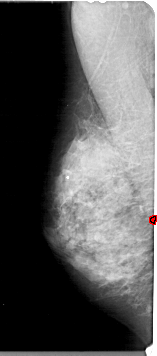

A_1926_1.RIGHT_MLO

RIGHT_MLO LINES 5491 PIXELS_PER_LINE 2266 BITS_PER_PIXEL 12 RESOLUTION 43.5 NON_OVERLAY